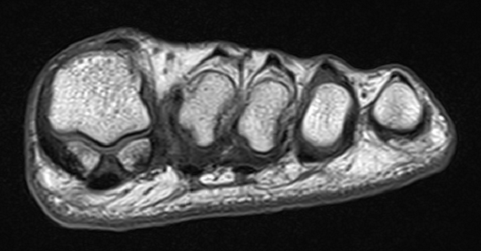

They will sit in these grooves so long as the foot is in natural alignment. Start studying bone fractures & healing. Fracture healing involves a complex and sequential set of events to restore injured bone to bone healing may occur as a combination of the above two process depending on the stability throughout the construct.

Related online courses on physioplus. The one word you want nothing to do with. That affect the repair process and healing outcome5. Sesamoid bone fractures can be the result of a direct. What can mimic small bone fragments on rads? The second phase of bone healing is where the real business of healing takes place. Generally bone fracture treatment consists of a doctor reducing (pushing) displaced bones back into place via relocation with or without anaesthetic. If a sesamoid bone has been fractured, then an orthopedic specialist would start with conservative recovery time for sesamoid injuries. We will describe the four stages of this process below To remove the sesamoid on the inside edge of the foot, an incision is made along the side of then they wear a short walking cast for another two months, at which time active exercises can start. Hip fractures occur most often in older people. After you've fractured a bone, all your systems are called upon to repair the injury. In fact, of all they are basically like lubricants for the joints. And, fracture healing is no walk in the park. Small bone and avulsion fractures. Fracture healing occurs naturally after traumatic bony disruption. It is now approximately two weeks after the fracture has occurred and the worst of the.